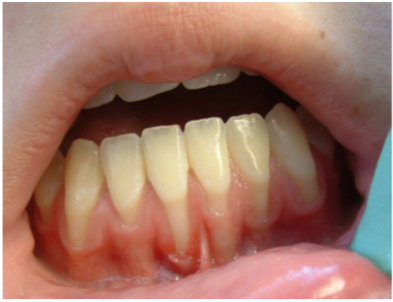

Figure 9 - Gingival recession Courtesy of Dentalcare.com

Figure 9

The most notable health consequences associated with spit tobacco use are those seen in the oral cavity. These effects can be recognized by the patient as well as the clinician and provide excellent opportunities to educate the user in the dangers of the tobacco use. Spit tobacco use causes serious short-term health consequences among young people. These consequences include halitosis, staining, abrasion of the teeth, gingivitis, gum recession, dental caries, and tooth loss.

Tooth loss is more common among spit tobacco users than nonusers. This loss is a result of several factors including poor oral hygiene, extensive decay, and destructive periodontitis. Focal gingival recession with periodontal attachment loss and bone erosion occurs frequently on the facial surfaces of the teeth where the tobacco is held. This recession is a result of the irritation caused by the toxic chemicals and abrasives found in spit tobacco. It is not uncommon to find substantial amounts of root surfaces exposed at the tobacco placement site. With the root surface exposed, there is increased risk of hot and cold sensitivity and root decay. While gingivitis may be present, bleeding is less common because of the vasoconstriction properties of nicotine. Instead, the heavy spit tobacco user will likely develop gingival swelling and bleeding as a result of poor oral hygiene.